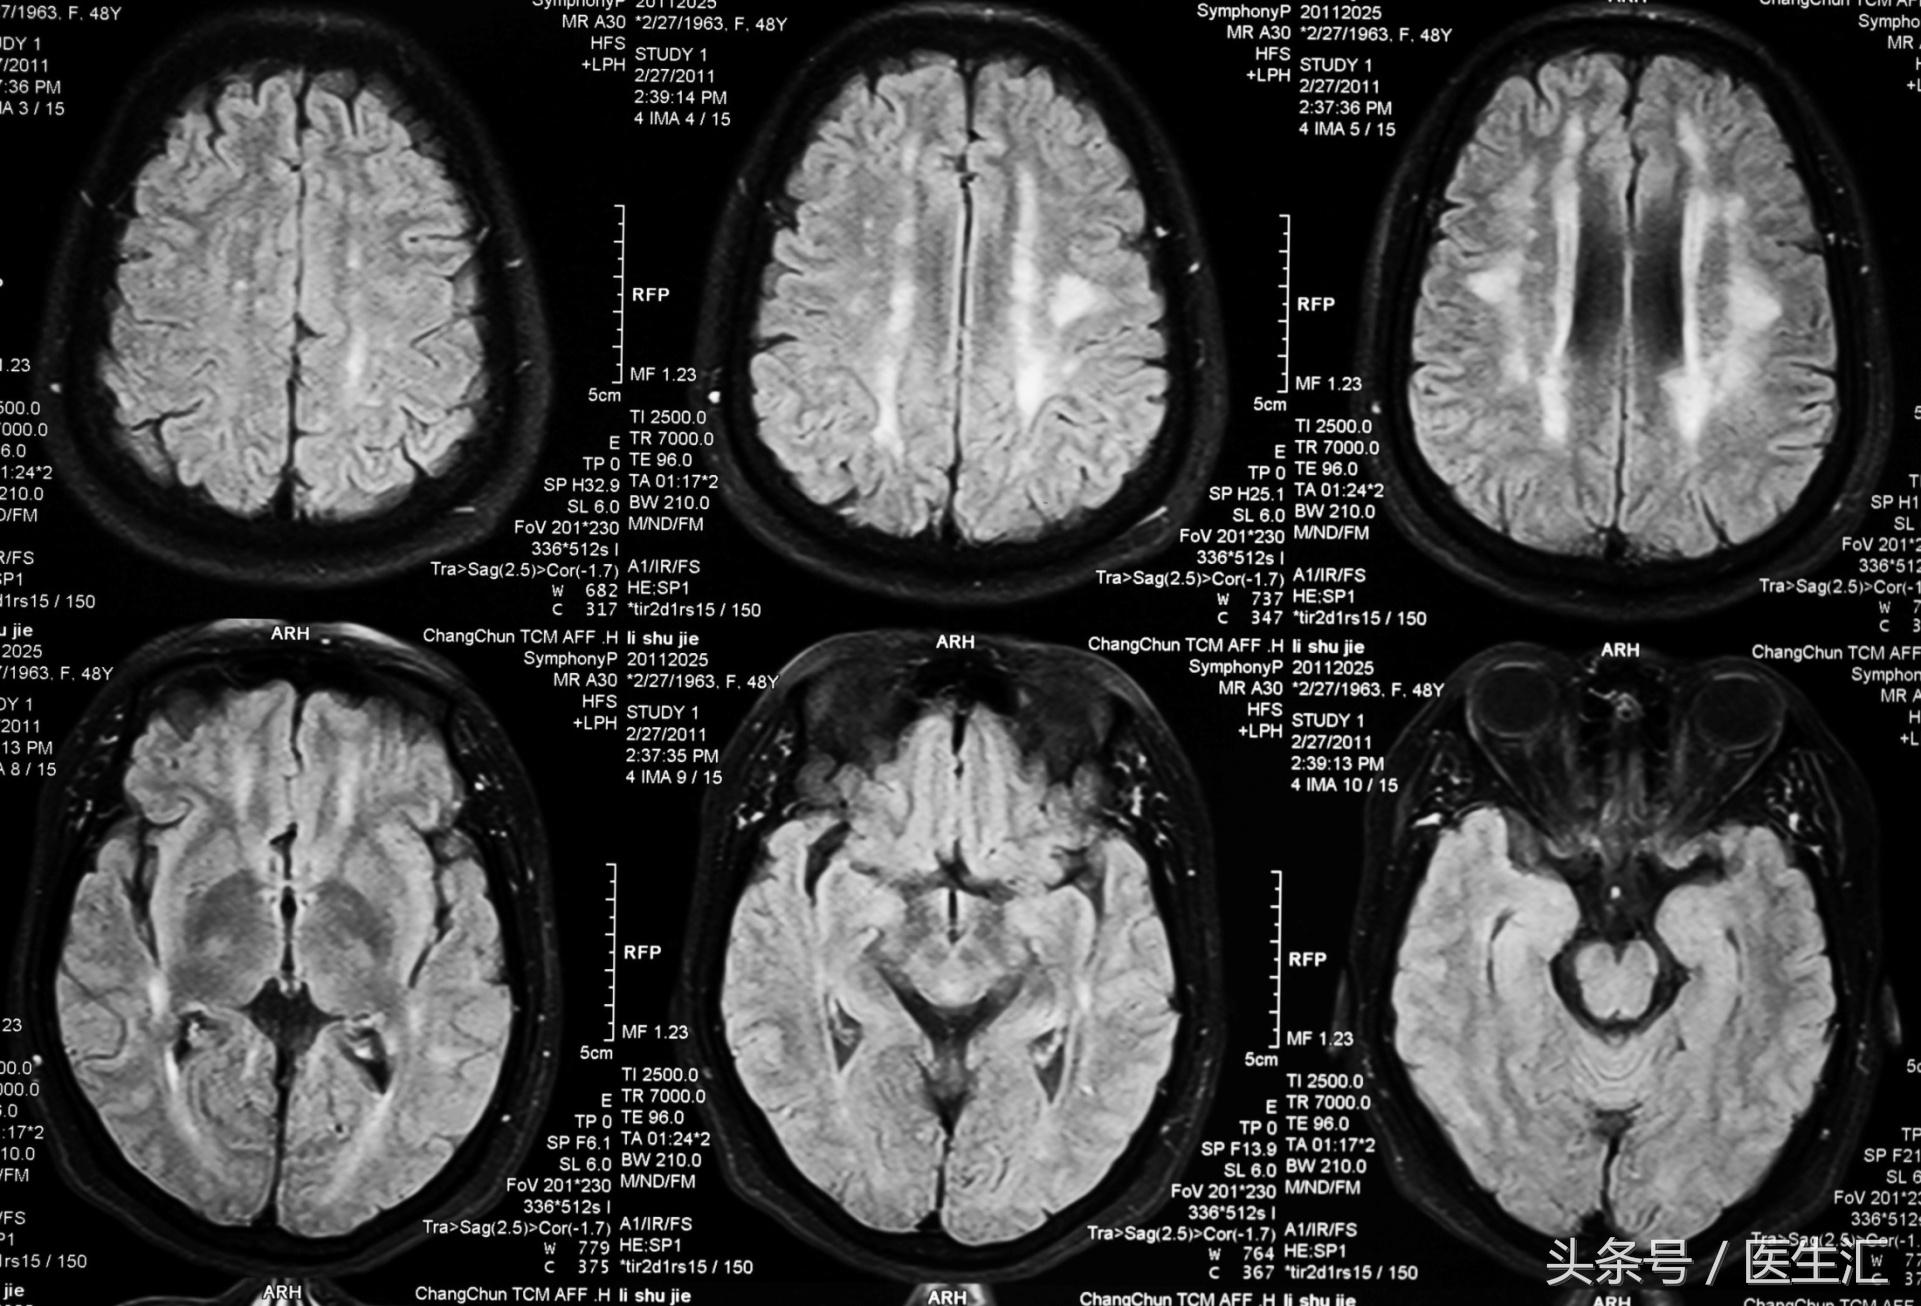

头颅MRI:(见图1)

专家判读:双侧弥漫脑白质病变